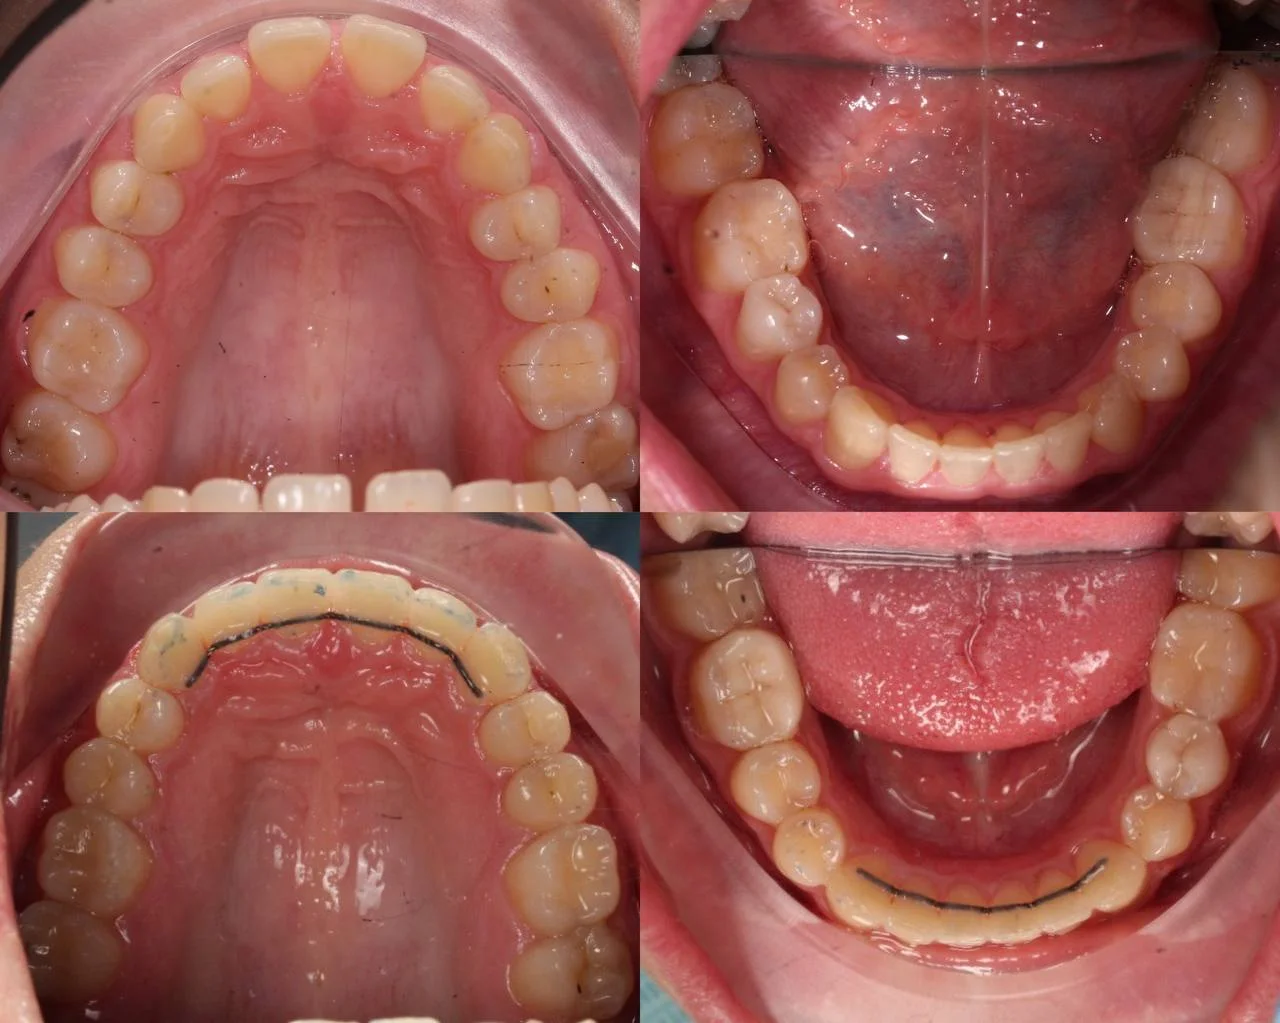

Зубы выровнены, смыкание нормализовано. Установлены несъёмные ретейнеры на обе челюсти, сняты сканы для ретенционных кап. Консультация ортопеда запланирована на более поздний срок.

Решение: Поставили прозрачные элайнеры 3D Smile на обе челюсти. Начали с набора из 34 кап, но в процессе стало понятно, что для полной коррекции нужна доработка — заказали дополнительный набор из 28 кап. Это нормальная ситуация: организм реагирует на перемещение зубов индивидуально, и заранее предсказать точное количество кап до последней штуки невозможно. В итоге 62 капы за 32 месяца — зубы встали на место, смыкание пришло в норму. Параллельно следили за гигиеной, чтобы дёсны оставались здоровыми на протяжении всего лечения.

Основной набор из 34 кап выполнил бо́льшую часть работы, но для финальной коррекции смыкания понадобился дополнительный комплект. Это не редкость — зубы двигаются с разной скоростью, и последние доли миллиметра часто требуют доработки. В итоге получили стабильный результат, который зафиксировали ретейнерами.